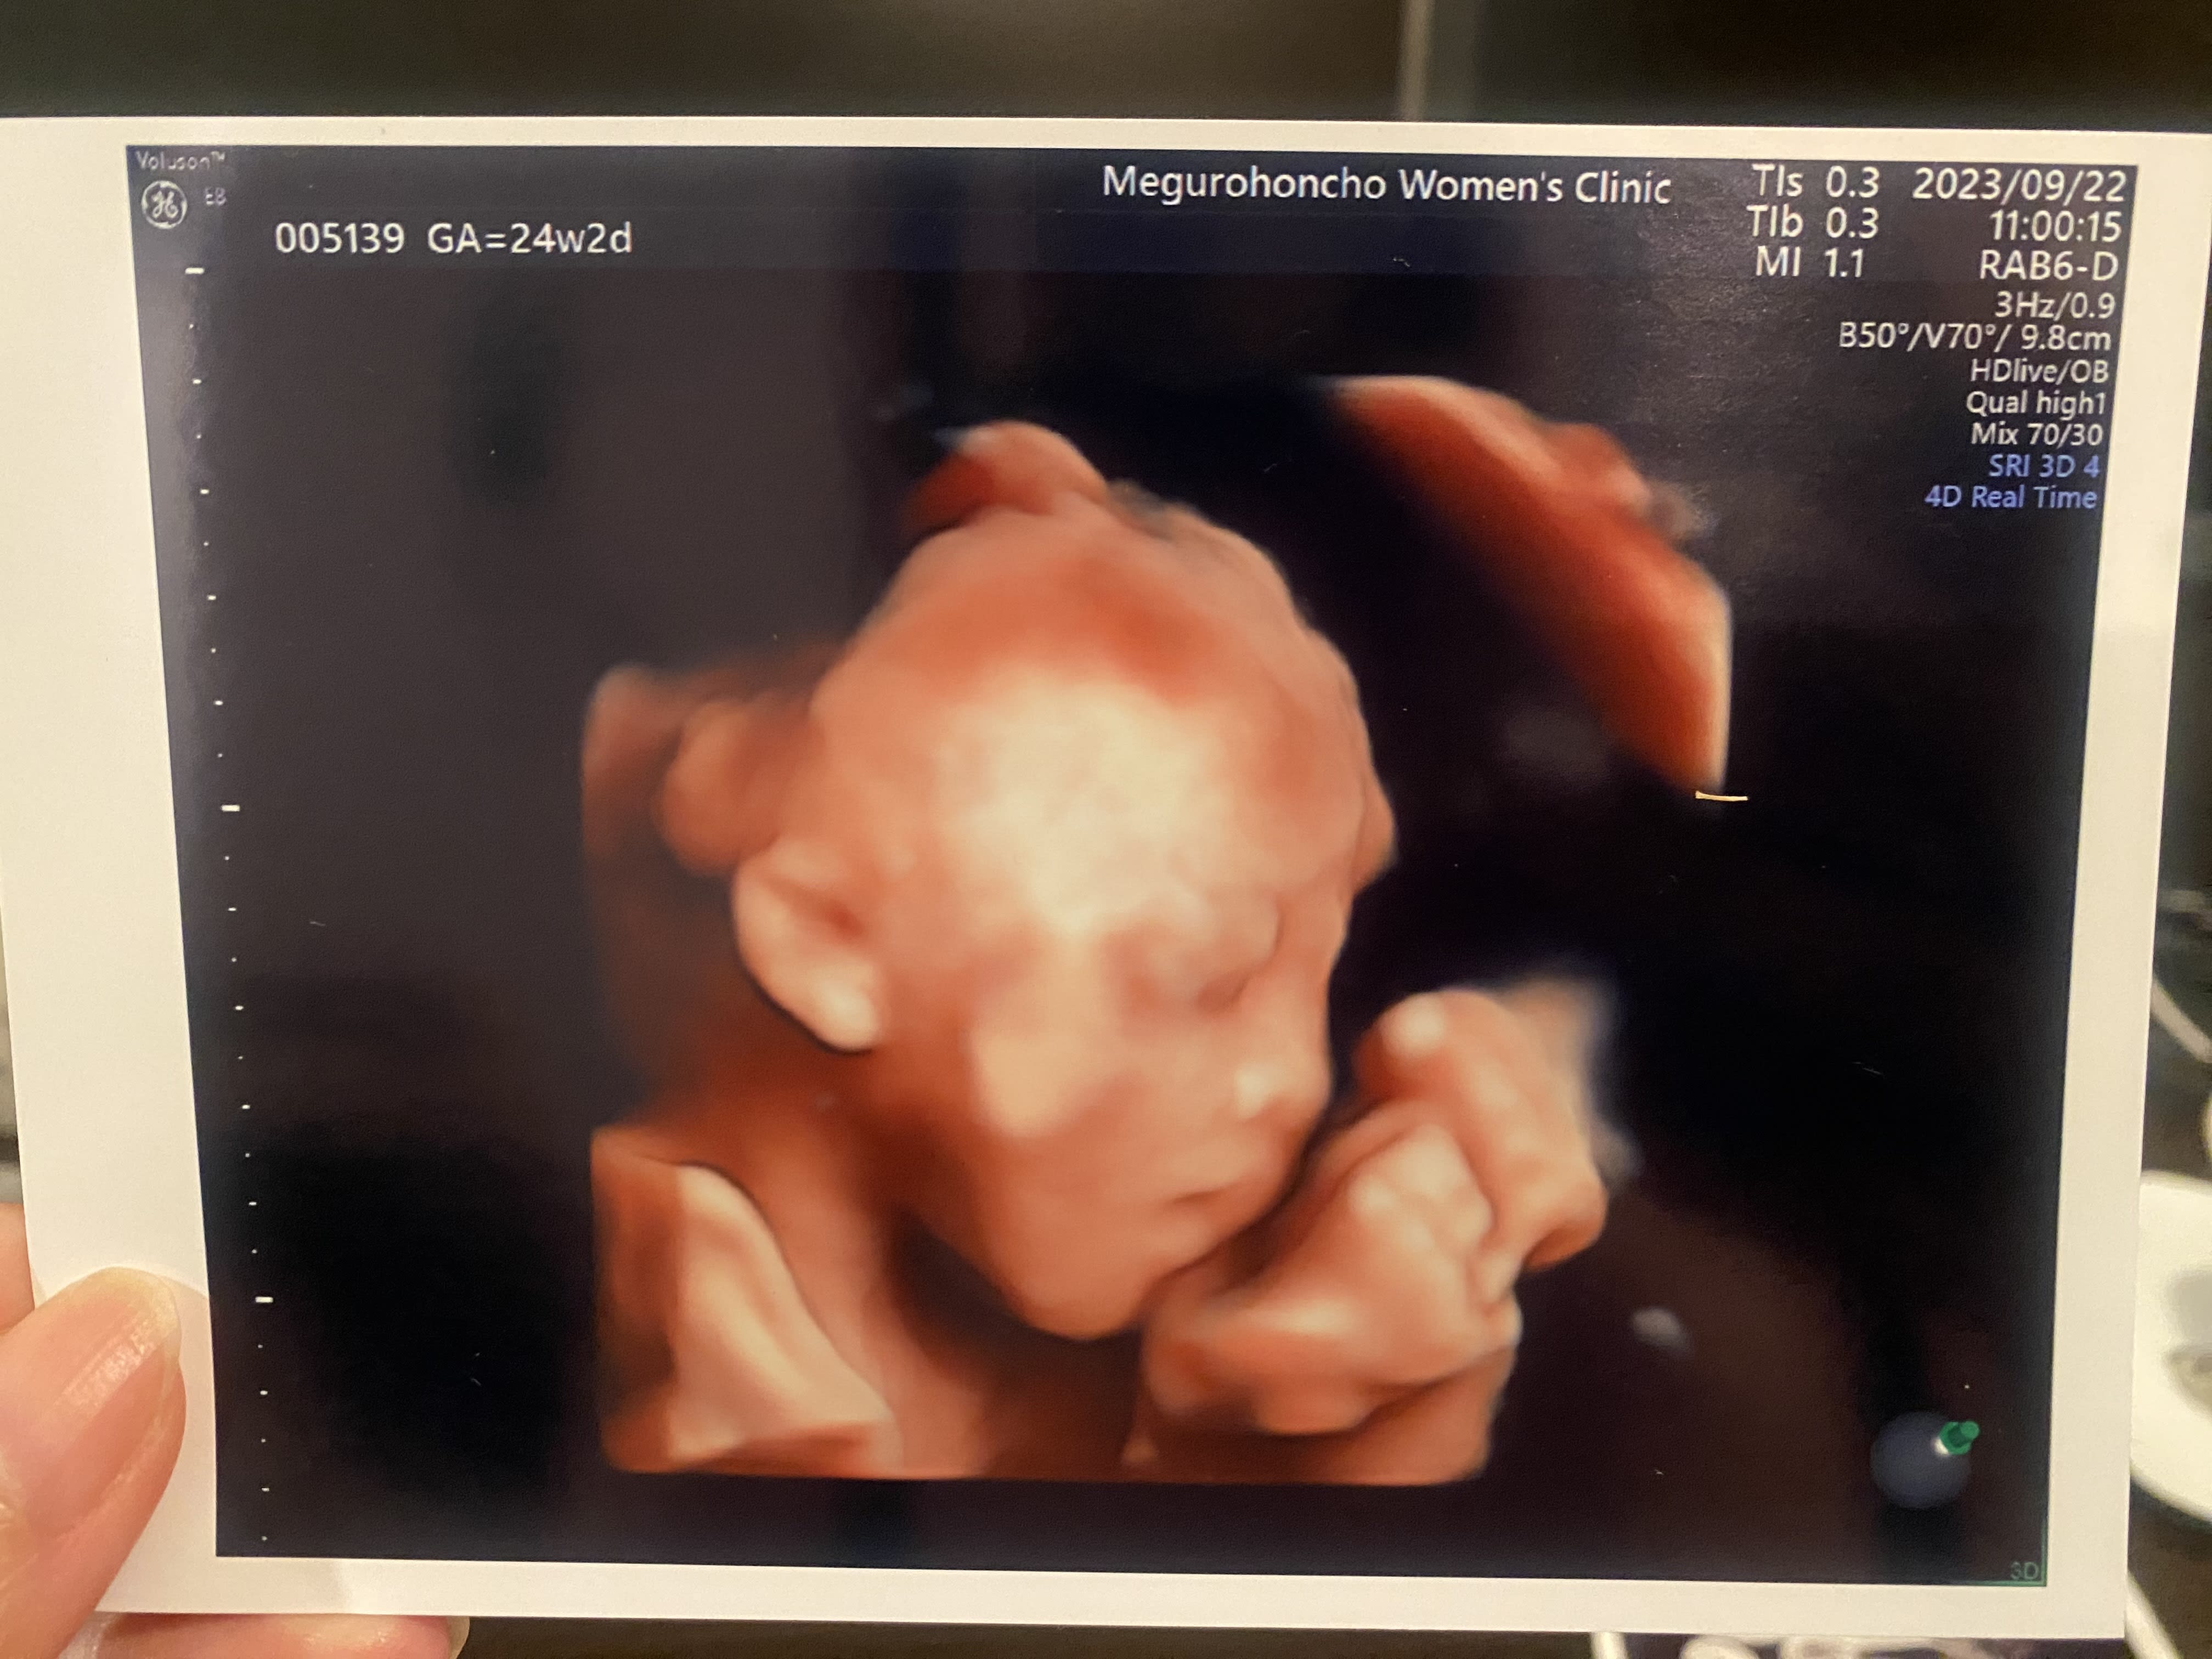

24週の4Dエコー。 唇が大きくて、パパに似てる気がする? 先生に男の子って言われたよ😊